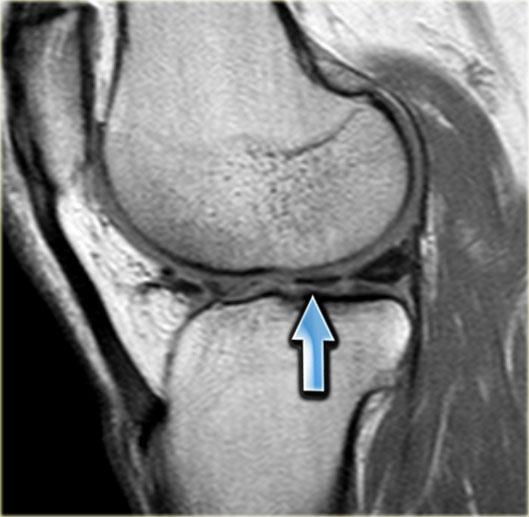

Trước tiên hãy quan sát hình ảnh bên trái và cố gắng nhận diện vị trí rách sụn chêm.

Những tổn thương rách này thường dễ bị bỏ sót.

Ghi nhận một đường rách hướng tâm tại vị trí chân sụn chêm phía sau của sụn chêm trong, đường rách xuyên suốt toàn bộ chiều dày sụn chêm với hình ảnh khe dịch lan dọc theo khuyết tổn thương (mũi tên đỏ).

Rách chân sụn chêm thường đi kèm với hiện tượng thoát vị sụn chêm ra ngoài bờ mâm chày.

Thoát vị sụn chêm trên 3 mm thường liên quan đến các tổn thương rách tại vùng chân sụn chêm (6).

Trong trường hợp bên trái, ghi nhận một đường rách hướng tâm hoàn toàn tách rời sừng sau khỏi chân bám của nó (mũi tên đỏ).

Ngoài ra còn có hình ảnh thoát vị sụn chêm mức độ tối thiểu (hình 1/6).

Đây là một trường hợp rách chân sụn chêm trong khác.

Lưu ý rằng sừng sau không còn bám vào xương chày.

Thay vào đó, có thể thấy một khoảng hở (mũi tên cong).

Những tổn thương rách này rất dễ bị bỏ sót khi người đọc nhầm tưởng sừng sau vẫn bình thường.

Đây là một trường hợp điển hình khác của rách chân sụn chêm trong.

Lưu ý rằng trường hợp này còn kèm theo hình ảnh sụn chêm ngoài dạng đĩa.